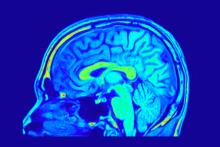

Лабораторни изследвания са установили връзка между осъзнатите сънища и една форма на електрическа активност в мозъка - "гама вълните" във фронталния и страничните дялове, които могат да бъдат разчетени в електроенцефалограмата (ЕЕГ). Но естеството на тази връзка остава неясно досега.

След три минути непрекъснат парадоксален сън учените изпратили през черепа слаб електрически импулс към фронталните и страничните дялове на мозъка, което е безболезнена процедура.